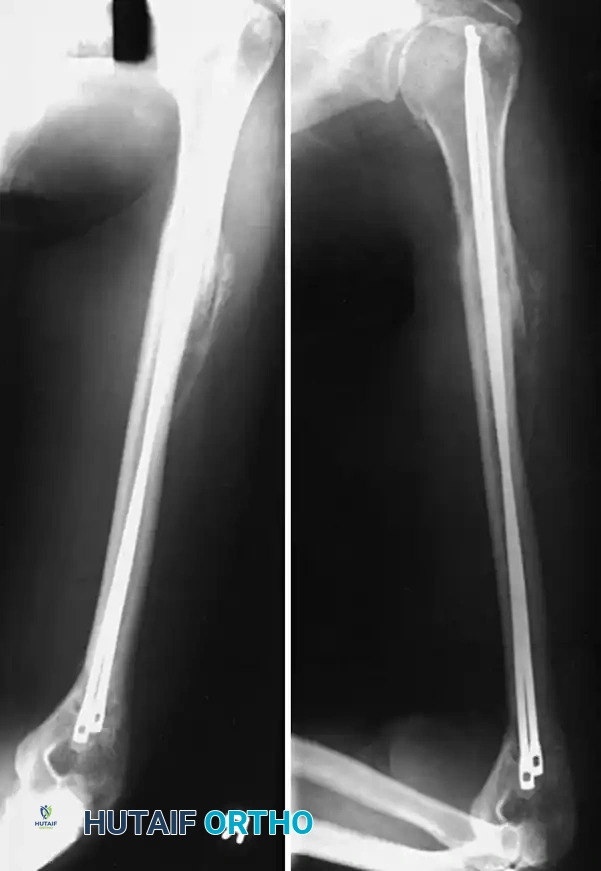

INTRAMEDULLARY FIXATION OF THE HUMERAL SHAFT

The undeniable success of intramedullary (IM) nailing in lower extremity trauma (femur and tibia) historically led to immense enthusiasm for its application in the humeral shaft. Biomechanically, IM nails act as load-sharing devices, situated at the mechanical axis of the bone, thereby subjecting the implant to less bending stress compared to eccentric plate fixation.

However, the humerus is not a weight-bearing bone, and its primary biomechanical forces are torsional rather than axial. While literature reports excellent union rates with nailing techniques, significant problems regarding insertion site morbidity—specifically shoulder pain and rotator cuff pathology—have dampened the initial enthusiasm.

The advent of locking IM nails revolutionized rotational control and axial stability. However, early generations of locked nails were bulky, requiring extensive reaming of the medullary canal. This often led to fracture distraction, particularly in patients with narrow isthmuses. Modern humeral nails are designed in smaller diameters (7, 8, or 9 mm) to accommodate smaller bones and can be inserted in either a reamed or unreamed fashion.

Preferred Technique: Rigid Antegrade Locked Nailing

For the majority of indications (segmental fractures, proximal-to-middle third junctions, pathological fractures, and polytrauma), rigid, locked antegrade nailing is the preferred modality.

- Guide Wire Placement: Pass a ball-tipped guide wire across the fracture site into the distal metaphysis under fluoroscopic guidance.

- Canal Preparation: If reaming is elected (to allow for a larger, more biomechanically stable nail), ream sequentially over the guide wire. Ensure the soft tissues are protected at the entry site.

- Nail Insertion: Insert the selected rigid IM nail over the guide wire. Avoid excessive forceful impaction to prevent iatrogenic comminution.

- Proximal Locking: Utilize the outrigger targeting device to insert the proximal locking screws. Ensure the axillary nerve is protected during this step by using soft tissue sleeves.

- Distal Locking and Confirmation: Perform distal locking using a freehand fluoroscopic technique. Confirm anatomic reduction, restoration of length and rotation, and accurate screw placement with orthogonal fluoroscopic views.